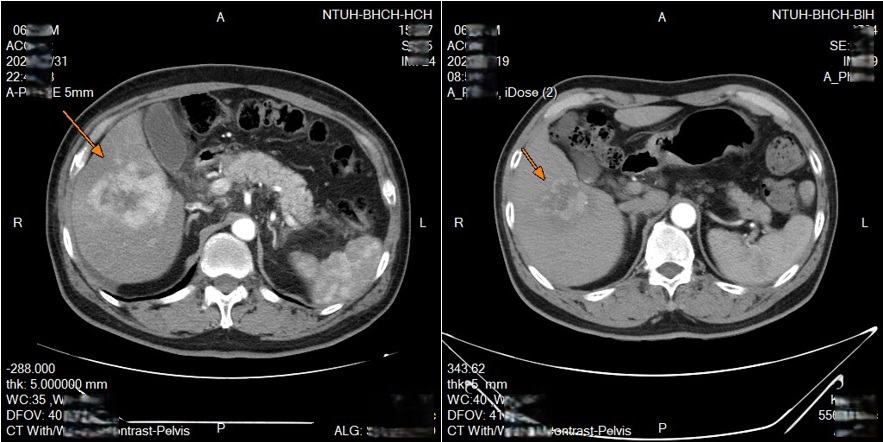

圖:鎖骨下導管置放進行肝動脈內灌注化療,兩次療程後腫瘤明顯縮小。(左:治療前/右:兩次療程後)/新竹臺大醫院提供

新竹臺大分院收治一名63歲男性,先是得了淋巴癌,而後在治療期間又發現肝腫瘤,確診肝癌。經醫療團隊與病人充分討論後,安排進行鎖骨下導管置放於肝動脈灌注化療,歷經兩次療程腫瘤明顯縮小。

透過可移動式的導管放置,每次治療後都可以重新調整導管的位置,若導管移位或堵塞,可以迅速處理,從而達到更好的治療效果,並且減少併發症的發生。臨床上,不少病人對治療產生良好反應,部分病人在影像追蹤中可見腫瘤縮小或消失,顯示治療具相當潛力。